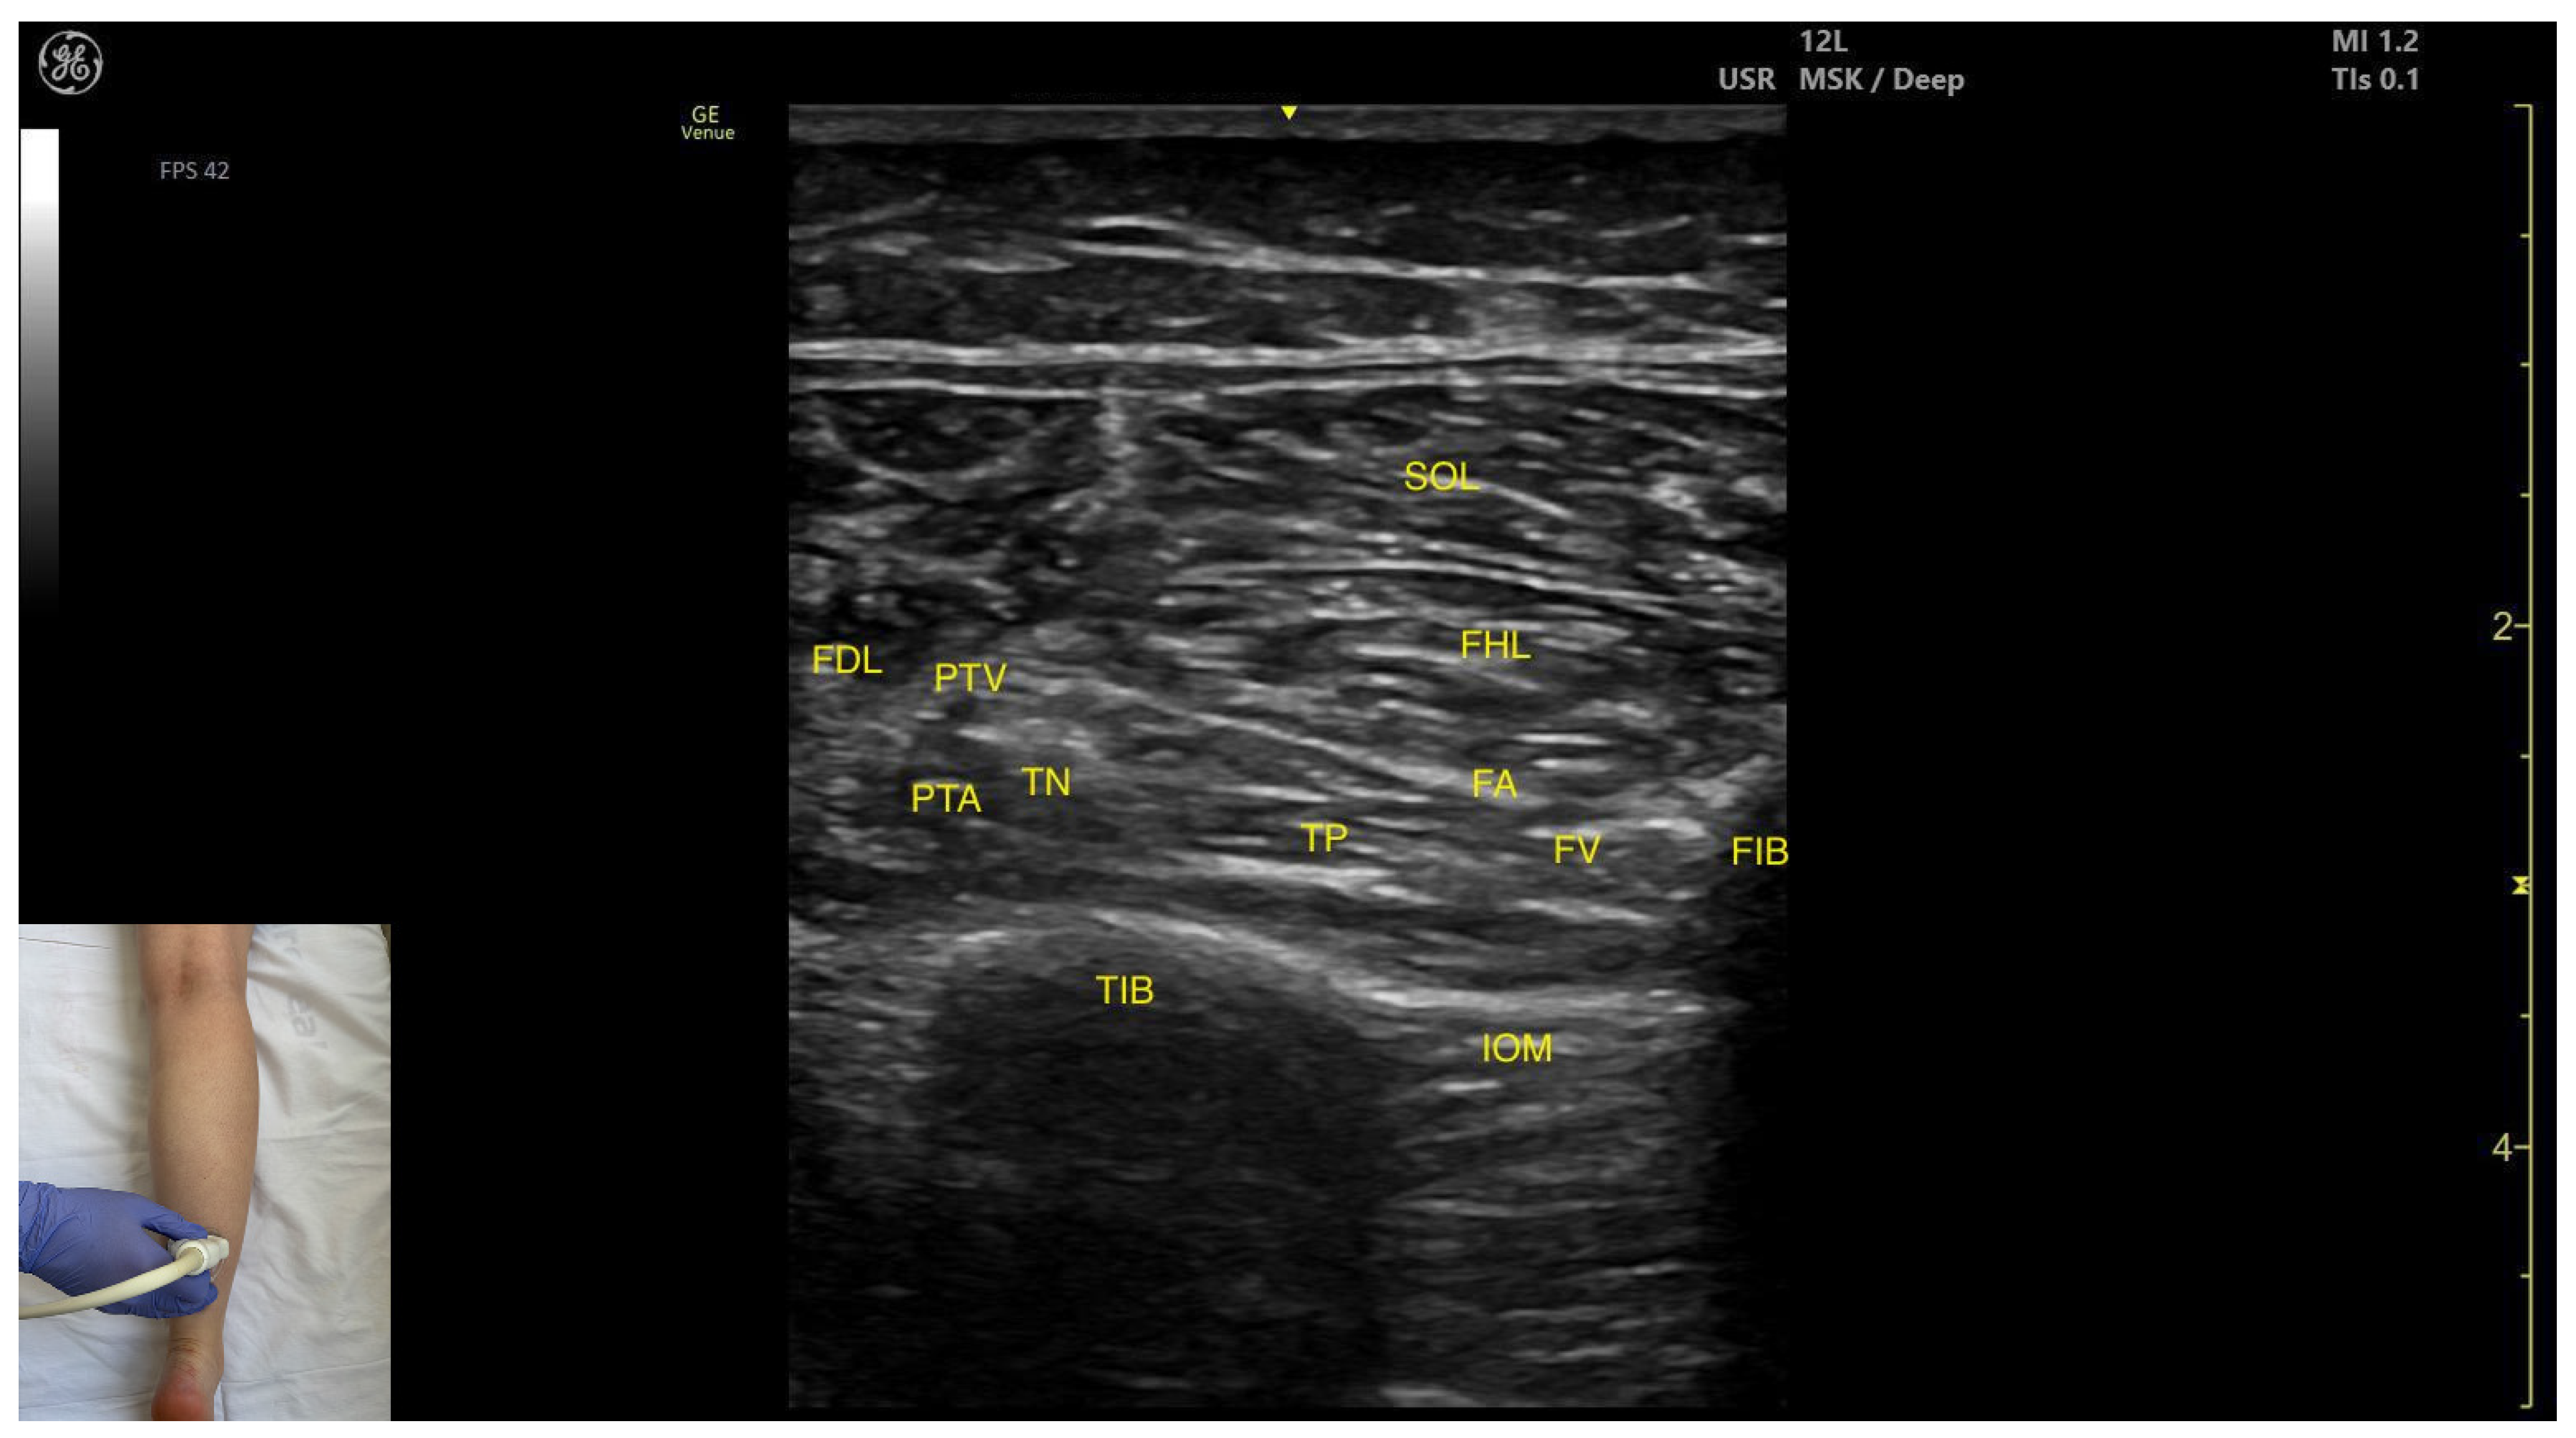

3.3.3. Medial Window

Ultrasound Identification

Key Ultrasound Landmarks

- Muscle position: The tibialis posterior is the deepest muscle in the posterior compartment of the leg. It is bordered superficially and medially by the flexor digitorum longus and superficially and laterally by the flexor hallucis longus. The interosseous membrane lies deep to the TP.

- Neurovascular bundle: Within the intermuscular fascial plane between the flexor digitorum longus, flexor hallucis longus, and soleus, the tibial nerve, posterior tibial artery, and posterior tibial vein are situated.

- External fascia: The TP does not have a well-defined fascia that separates it from flexor digitorum longus and flexor hallucis longus, during BoNT-A injection.

- Dynamic evaluation: Muscle contraction becomes evident during ankle inversion and plantar flexion at the ankle joint.

3.4. Flexor Hallucis Longus (FHL)

3.4.1. Overview

3.4.2. Ultrasound Identification

3.4.3. Key Ultrasound Landmarks

- Muscle morphology: It is a strong, unipennate muscle. In our clinical practice it is referred to as the “shark tail”

- Muscle position: It is located superficial to the fibular cortex. The SOL lies superficial to the FHL. Deep and medial to it lies the tibialis posterior (TP) and, deep to TP, the interosseous membrane. Medial to this region is the flexor digitorum longus (FDL). At this level, the usual anatomical relationship of the FHL and FDL is paradoxically reversed.

- Neurovascular bundle: The tibial nerve, posterior tibial artery, and posterior tibial vein lie within the intermuscular fascia between tibialis posterior, SOL, FDL.

- External fascia: The FHL has a well-defined fascia that separates it from soleus, aiding in safe BoNT-A injection. It does not have a pronounced fascia that separates it from the tibialis posterior and flexor digitorum longus.

- Dynamic evaluation: During dynamic evaluation, scanning proximally toward the knee joint, the FHL muscle thickness decreases, and it disappears from view, while the soleus thickens and the lateral head of the gastrocnemius appears superficially (Video S1). Muscle contraction is seen during flexion of the hallux at the metatarsophalangeal and interphalangeal joints, as well as during plantar flexion at the ankle joint.

3.5. Flexor Digitorum Longus (FDL)

3.5.1. Overview

3.5.2. Ultrasound Identification

3.5.3. Key Ultrasound Landmarks

- Muscle position: It is located in the medial compartment of the posterior leg. Superficially, it is covered by the soleus; lateral to the FDL lies the flexor hallucis longus; deep and lateral to it lie the TP with the interosseous membrane located beneath it. At this level, the flexor digitorum longus and flexor hallucis longus are paradoxically reversed in position relative to their usual anatomical course.

- Neurovascular bundle: Within the intermuscular fascia between the flexor digitorum longus, flexor hallucis longus, and soleus are the tibial nerve, posterior tibial artery, and posterior tibial veins.

- External fascia: The FDL has a well-defined fascia that separates it from the soleus, which is relevant during BoNT-A injection. It does not have a pronounced fascia that separates it from the flexor hallucis longus and tibialis posterior.

- Dynamic evaluation: During dynamic evaluation, scanning proximally toward the knee joint, the flexor digitorum longus decreases in thickness and disappears from view, while the soleus increases in size and the medial head of the gastrocnemius appears superficial to the soleus (Video S2). Muscle contraction is visible during flexion of toes II–V (at metatarsophalangeal, proximal and distal interphalangeal joints) and ankle plantar flexion.